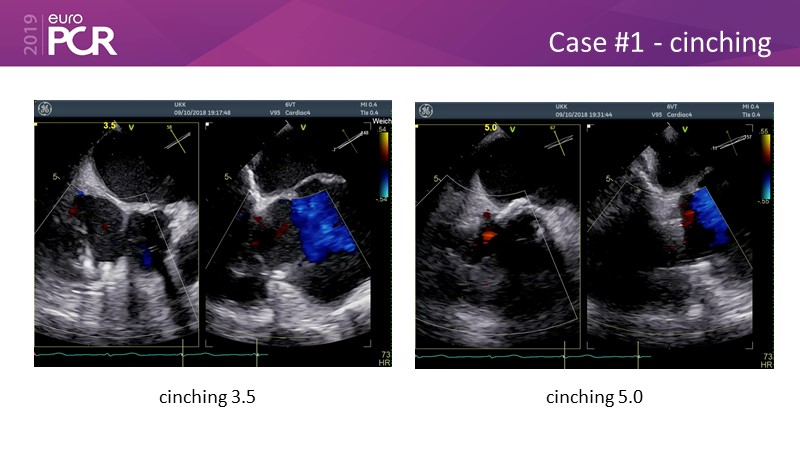

Addressing tricuspid regurgitation with annular reduction: the Cardioband tricuspid system

Consult this session to understand how patients with tricuspid regurgitation and annular dilatation can benefit from Cardioband system...